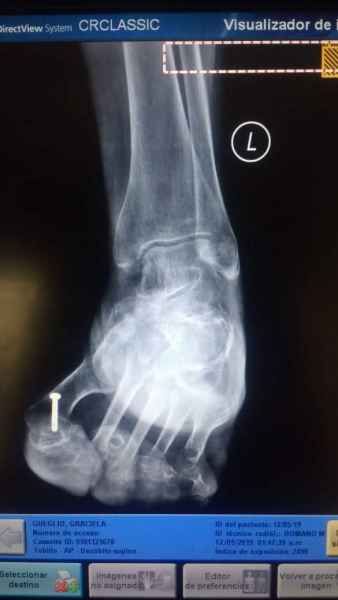

El pie es el órgano distintivo y característico de la especie humana, la única criatura que marcha erguida. El pie es una muy compleja estructura de arquitectura perfecta, adaptado a su función de apoyo, traslación, salto, con una riquísima sensibilidad que le permite detectar las más leves imperfecciones del suelo para estabilizar la marcha.

Tanto la estructura del pie como su funcionalismo que es la marcha, pueden ser asiento y manifestación respectivamente de alteraciones locales ó sistémicas, por lo que su cuidadoso examen resulta de extrema utilidad diagnóstica.